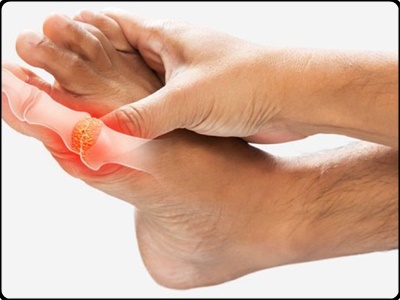

단백질이 체내에서 대사하는 동안 요산을 생성하는데 이를 정상적인 사람의 경우 신장을 통해 분해되어 몸밖으로 배출합니다. 하지만 요산의 과다하게 생성되거나 배출이 여의치 않는 경우 몸에 축적되면 발생하는 것이 통풍입니다. 겉으로 보여지지는 않지만 통증이 심해서 견디기 어려울 정도라고 합니다. 손가락 발가락 통풍 증상 핵심 3가지 및 아플통 바람풍 통풍 치료법에 대해 정리해보도록 하겠습니다.

바람풍 아플통이라고 해서 바람에 스치기만 해도 아픈 병을 통풍이라고 합니다. 그만큼 통증이 심해서 발작을 일으킬 정도라고 하니 그 고통이 얼마나 심할지 싶습니다. 그렇다면 이렇게 견디기 힘든 통풍 치료법은 있는 걸까요?